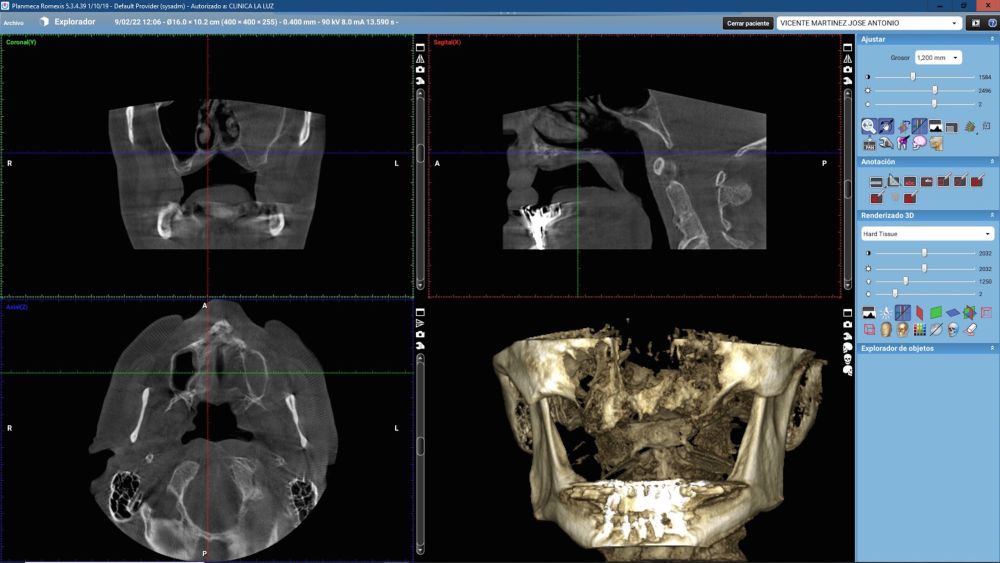

Introduction: Customized subperiosteal titanium implants, designed from planning and fabrication software, constitute an alternative in the rehabilitation of severe maxillary atrophy, avoiding more complex bone and soft reconstruction surgeries and reducing healing times. The aim of this article is to present the rehabilitation in a clinical case with severe atrophy in the upper jaw, using a structure with subperiosteal implants, by means of a digital protocol.

Clinical Case: A subperiosteal sintered titanium structure was fabricated with six transepithelial connections that were rehabilitated with an immediate implant supported fixed prosthesis made of PMMA. Two months later, a sintered chromium-cobalt framework with machined bases covered with acrylic resin teeth was fabricated as the final restoration. At one year follow-up, the case remains stable.

The objective of this work is to present implant-supported rehabilitation in a clinical case with severe atrophy in the upper maxilla, using a structure with subperiosteal implants, through a digital protocol, and the evolution one year after its placement.